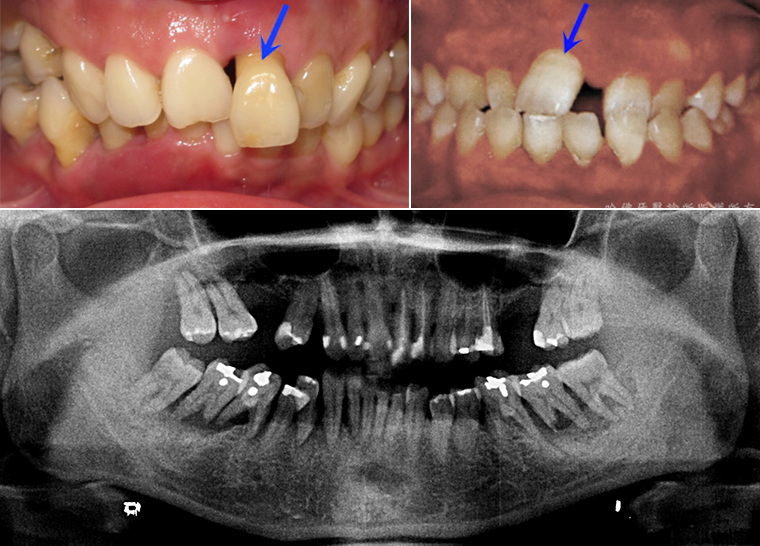

當蛀牙尚在輕微的時候缺乏臨床症狀,蛀牙經常在嚴重時才出現酸痛腫脹等症狀。而當酸痛腫脹等症狀出現時,蛀牙已相當嚴重「而不」易治療(圖3)。

(圖3)當蛀牙尚在輕微的時候缺乏臨床症狀,蛀牙經常在嚴重時才出現酸痛腫脹等症狀。而當酸痛腫脹等症狀出現時,蛀牙已相當嚴重「而不」易治療。

臨床上最多見的因牙周病而牙齒不正常移動案例,是上顎門齒漸漸外移。(圖6)。

(圖6)臨床上最多見的因牙周病造成牙齒不正常移動案例,使上顎門齒漸漸外移。